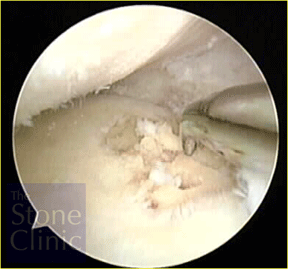

Microfracture was performed on an eburnated (lacking articular cartilage) area on the tibial plateau. The photo on the left shows the exposed bone where cartilage has been lost. The photo on the right shows the same area where microfracture is being performed by 'picking' through the surface to expose the bone marrow.

This next photo on the right shows the meniscal allograft in place. The meniscal allograft is the structure to the right of the photo. Above it is the rounded end of the femur and below is the flattened top of the tibia - the tibial plateau.